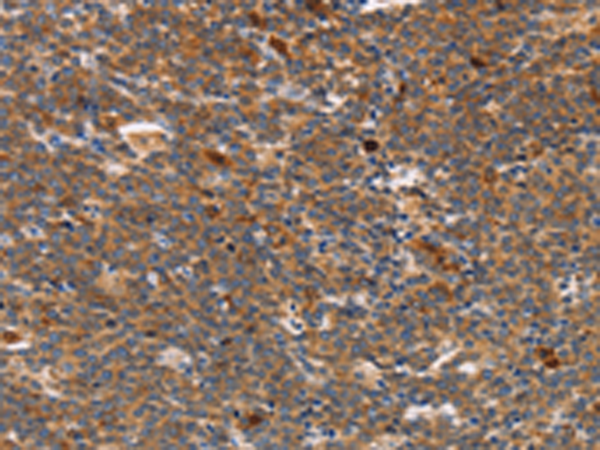

分类: 科研抗体货号: P11628别名: LEC; LMC; NCC4; CKb12; HCC-4; LCC-1; Mtn-1; NCC-4; SCYL4; ILINCK; SCYA16应用: WB,IHC反应种属: Human

分类: 科研抗体货号: P11664别名: CIB; CIBP; KIP1; PRKDCIP; SIP2-28应用: IHC反应种属: Human, Mouse, Rat

分类: 科研抗体货号: P11634别名: CD30; Ki-1; D1S166E应用: IHC反应种属: Human